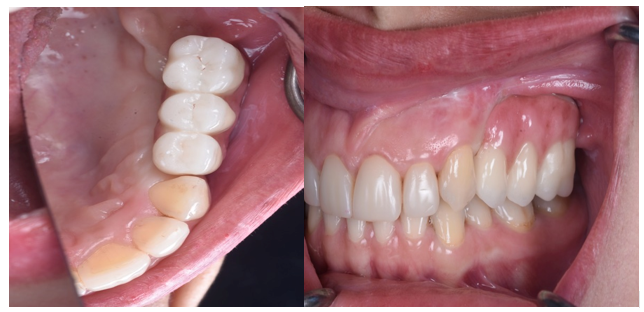

Post-operative imaging (Image 3) confirmed stable implant integration, and the patient underwent prosthetic rehabilitation with a fixed implant-supported prosthesis (Images 4, 5, and 6). Follow-up assessments showed optimal occlusion, favorable gingival adaptation, and high patient satisfaction.

Following distraction, the post-distraction radiograph (Image 2b) reveals successful vertical bone elongation. The post-implant and prosthesis image (Image 3) further demonstrates ideal implant placement and successful prosthetic integration. Intraoral photographs (Images 4 and 5) depict the final fixed prosthesis with harmonious gingival contours and alignment, while the frontal occlusion view (Image 6) confirms esthetic and functional restoration. The entire workflow from device installation to final rehabilitation is supported by radiographic and clinical validation.

3. Occlusal Intraoral Image: Final prosthesis aligned with natural dentition.

Fig 4: 1. Frontal Intraoral Image: Healthy gingival margins and anterior occlusion.

2. Lateral Intraoral Image: Right lateral view showing restored esthetics and function.